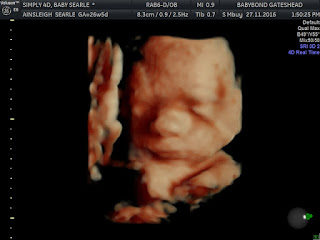

Anyway we went to get the 4D scan done today at BabyBond in Mothercare Team Valley, we decided to take Mason so he could see his little brother on the screen for the first time!........

Anyways here's the pictures and yes if anyone is thinking the same thing as both me and my husband ...he might aswell be masons twin, they are the spit and double of each other!!!

Why not check out my post from back when we had Masons 4D scan done to see just how similar they are!!